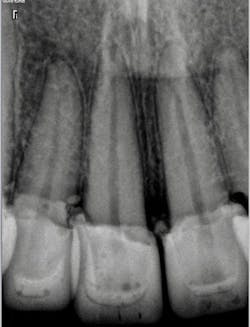

A 32-year-old male presented with having recent dental treatment abroad. Six maxillary anterior teeth had been individually crowned (figure 1).The patient’s chief complaint was severe pain in this area. He was unable to consume hot or cold food and drinks and could not use the teeth for incising. A radiographic exam revealed grossly overcontoured crowns, poorly fitting margins, and partially remaining cement (figure 2). The occlusion was evaluated and ruled out as the cause of pain. It was suspected after identifying the periapical radiolucency at the apex of the upper left lateral incisor that the pulps of some or all of the crowned teeth were affected.

Figure 1: Patient presentation with six maxillary anterior teeth individually crowned